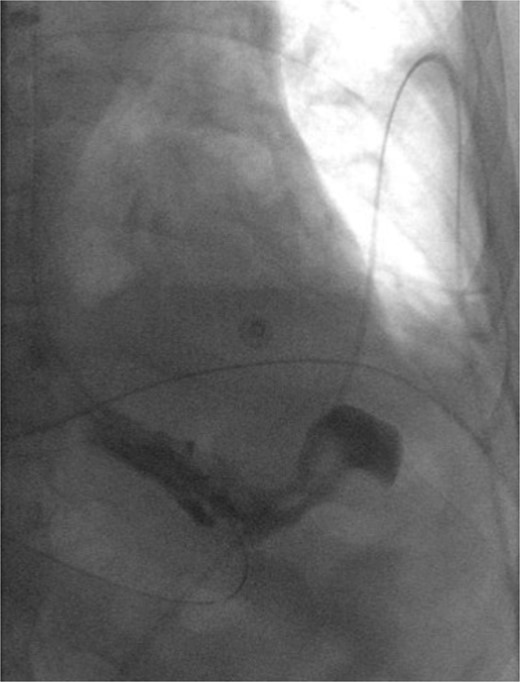

The patient was kept intubated given his hemodynamic lability. His postoperative course was complicated by new-onset atrial fibrillation with rapid ventricular response that resolved with beta-blockade. On post-operative day (POD) 2, barium swallow study was negative for contrast extravasation (Fig. 2). After advancing to a mechanical soft diet and obtaining clearance from physical therapy, the patient was discharged home on POD 8 in good condition. On POD 21, he presented to clinic endorsing post-prandial nausea and occasional emesis. Follow-up CT scan with oral contrast showed no evidence of hernia recurrence or gastric distention, and demonstrated adequate gastric emptying and contrast progression to the colon. He was then transitioned back to a liquid diet. At the 1-month post-operative visit, he was doing well and was encouraged to advance his diet as tolerated.

Barium swallow status post left diaphragmatic hernia repair without evidence of leak or proximal obstruction.